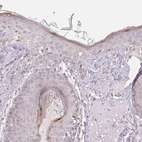

Immunohistochemistry analysis in human skin and skeletal muscle tissues using HPA031990 antibody. Corresponding KPRP RNA-seq data are presented for the same tissues.